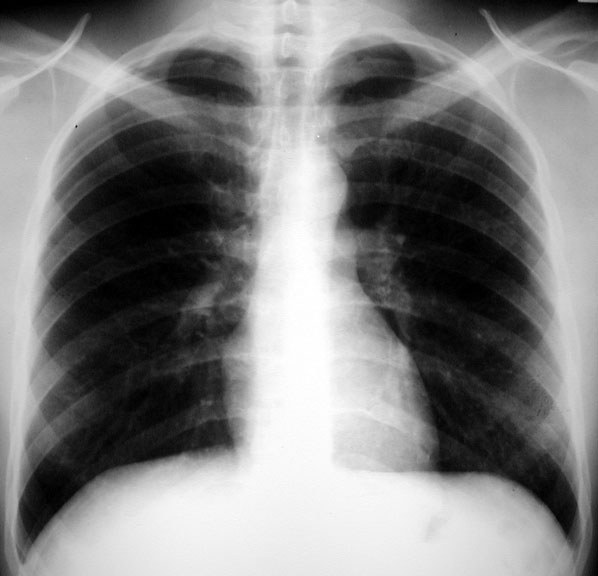

Lymphangitic Metastasis - Cancer Stomach

• Note progression of changes

Old film for comparison